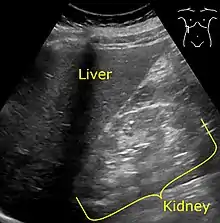

It is recommended that diabetics have their albumin levels checked annually, beginning immediately after a diagnosis of type 2 diabetes and five years after a diagnosis of type 1 diabetes.[15][18] Medical imaging of the kidneys, generally by ultrasonography, is recommended as part of a differential diagnosis if there is suspicion of urinary tract obstruction, urinary tract infection, kidney stones or polycystic kidney disease.[19] Conformation kidney biopsy should only be performed if non-diabetic kidney disease is suspected.